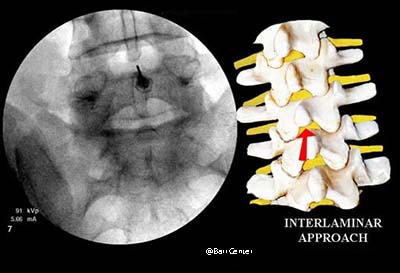

Interlaminar: the injection is usually midline and placed directly between two vertebrae (similar to the approach a woman undergoes during labor for epidural anesthesia).

With the interlaminar approach of an epidural steroid injection, the needle is passed between two vertebrae, usually midline. Contrast dye is injected to confirm proper needle position.